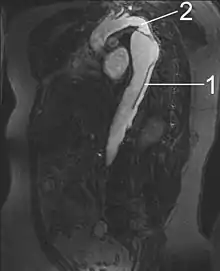

MRI

Magnetic resonance imaging (MRI) is also used for the detection and assessment of aortic dissection, with a sensitivity of 98% and a specificity of 98%. An MRI examination of the aorta produces a three-dimensional reconstruction of the aorta, allowing the physician to determine the location of the intimal tear and the involvement of branch vessels, and to locate any secondary tears. It is a noninvasive test, does not require the use of iodinated contrast material, and can detect and quantitate the degree of aortic insufficiency.

The disadvantage of the MRI scan in the face of aortic dissection is that it may be available only in larger hospitals, and the scan is relatively time-consuming, which could be dangerous in people who are already very unwell. Due to the high-intensity magnetic fields used during MRI, it cannot be used on individuals with metallic implants. In addition, some individuals experience claustrophobia while surrounded by the MRI magnet.

Serial imaging of the aorta is suggested, with MRI being the preferred imaging technique.